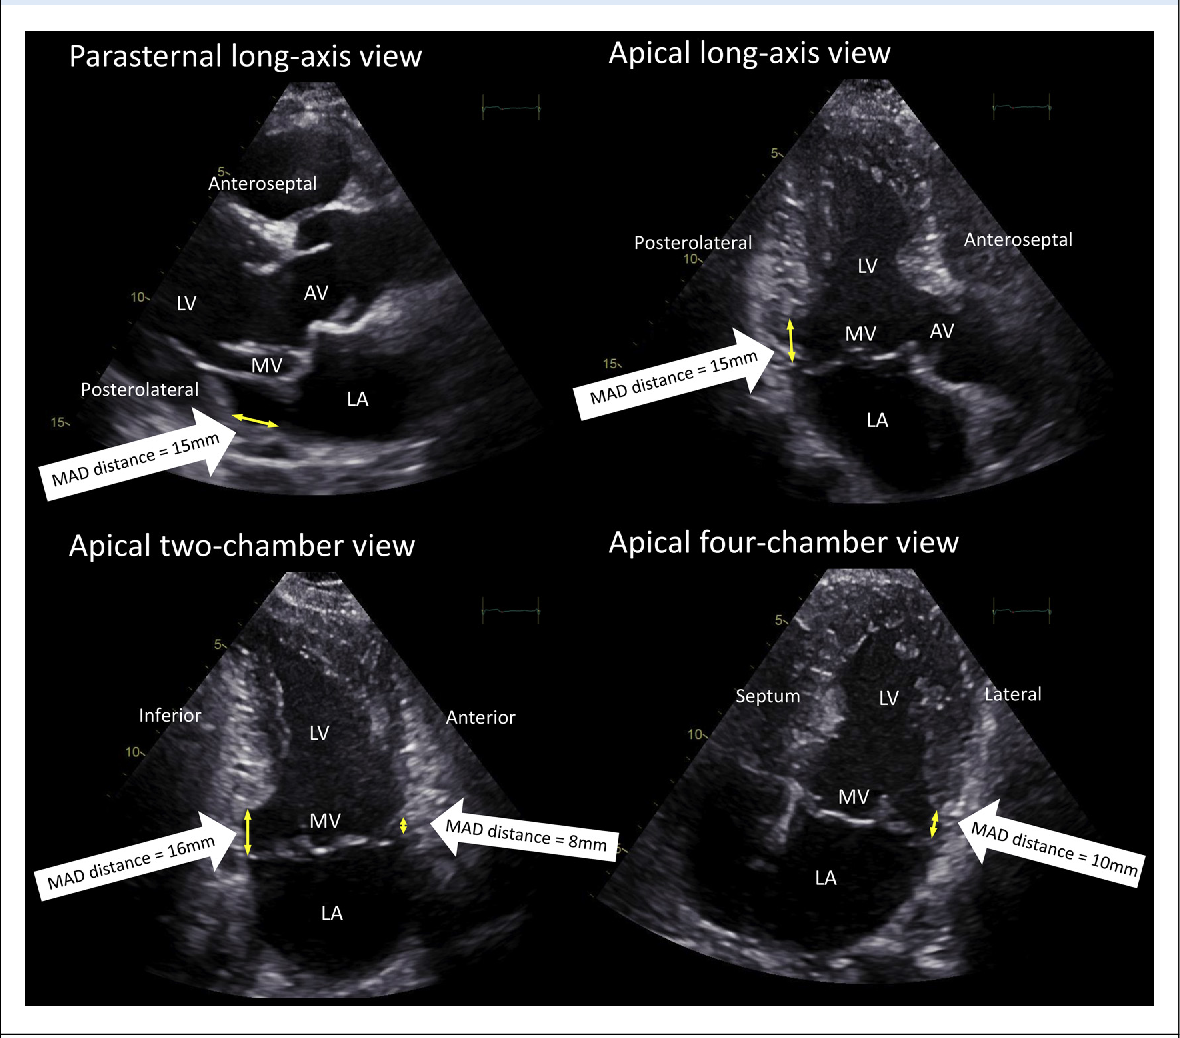

TitleSystolic blood pressure in babies of less than 32 weeks gestation in the first year of life ...